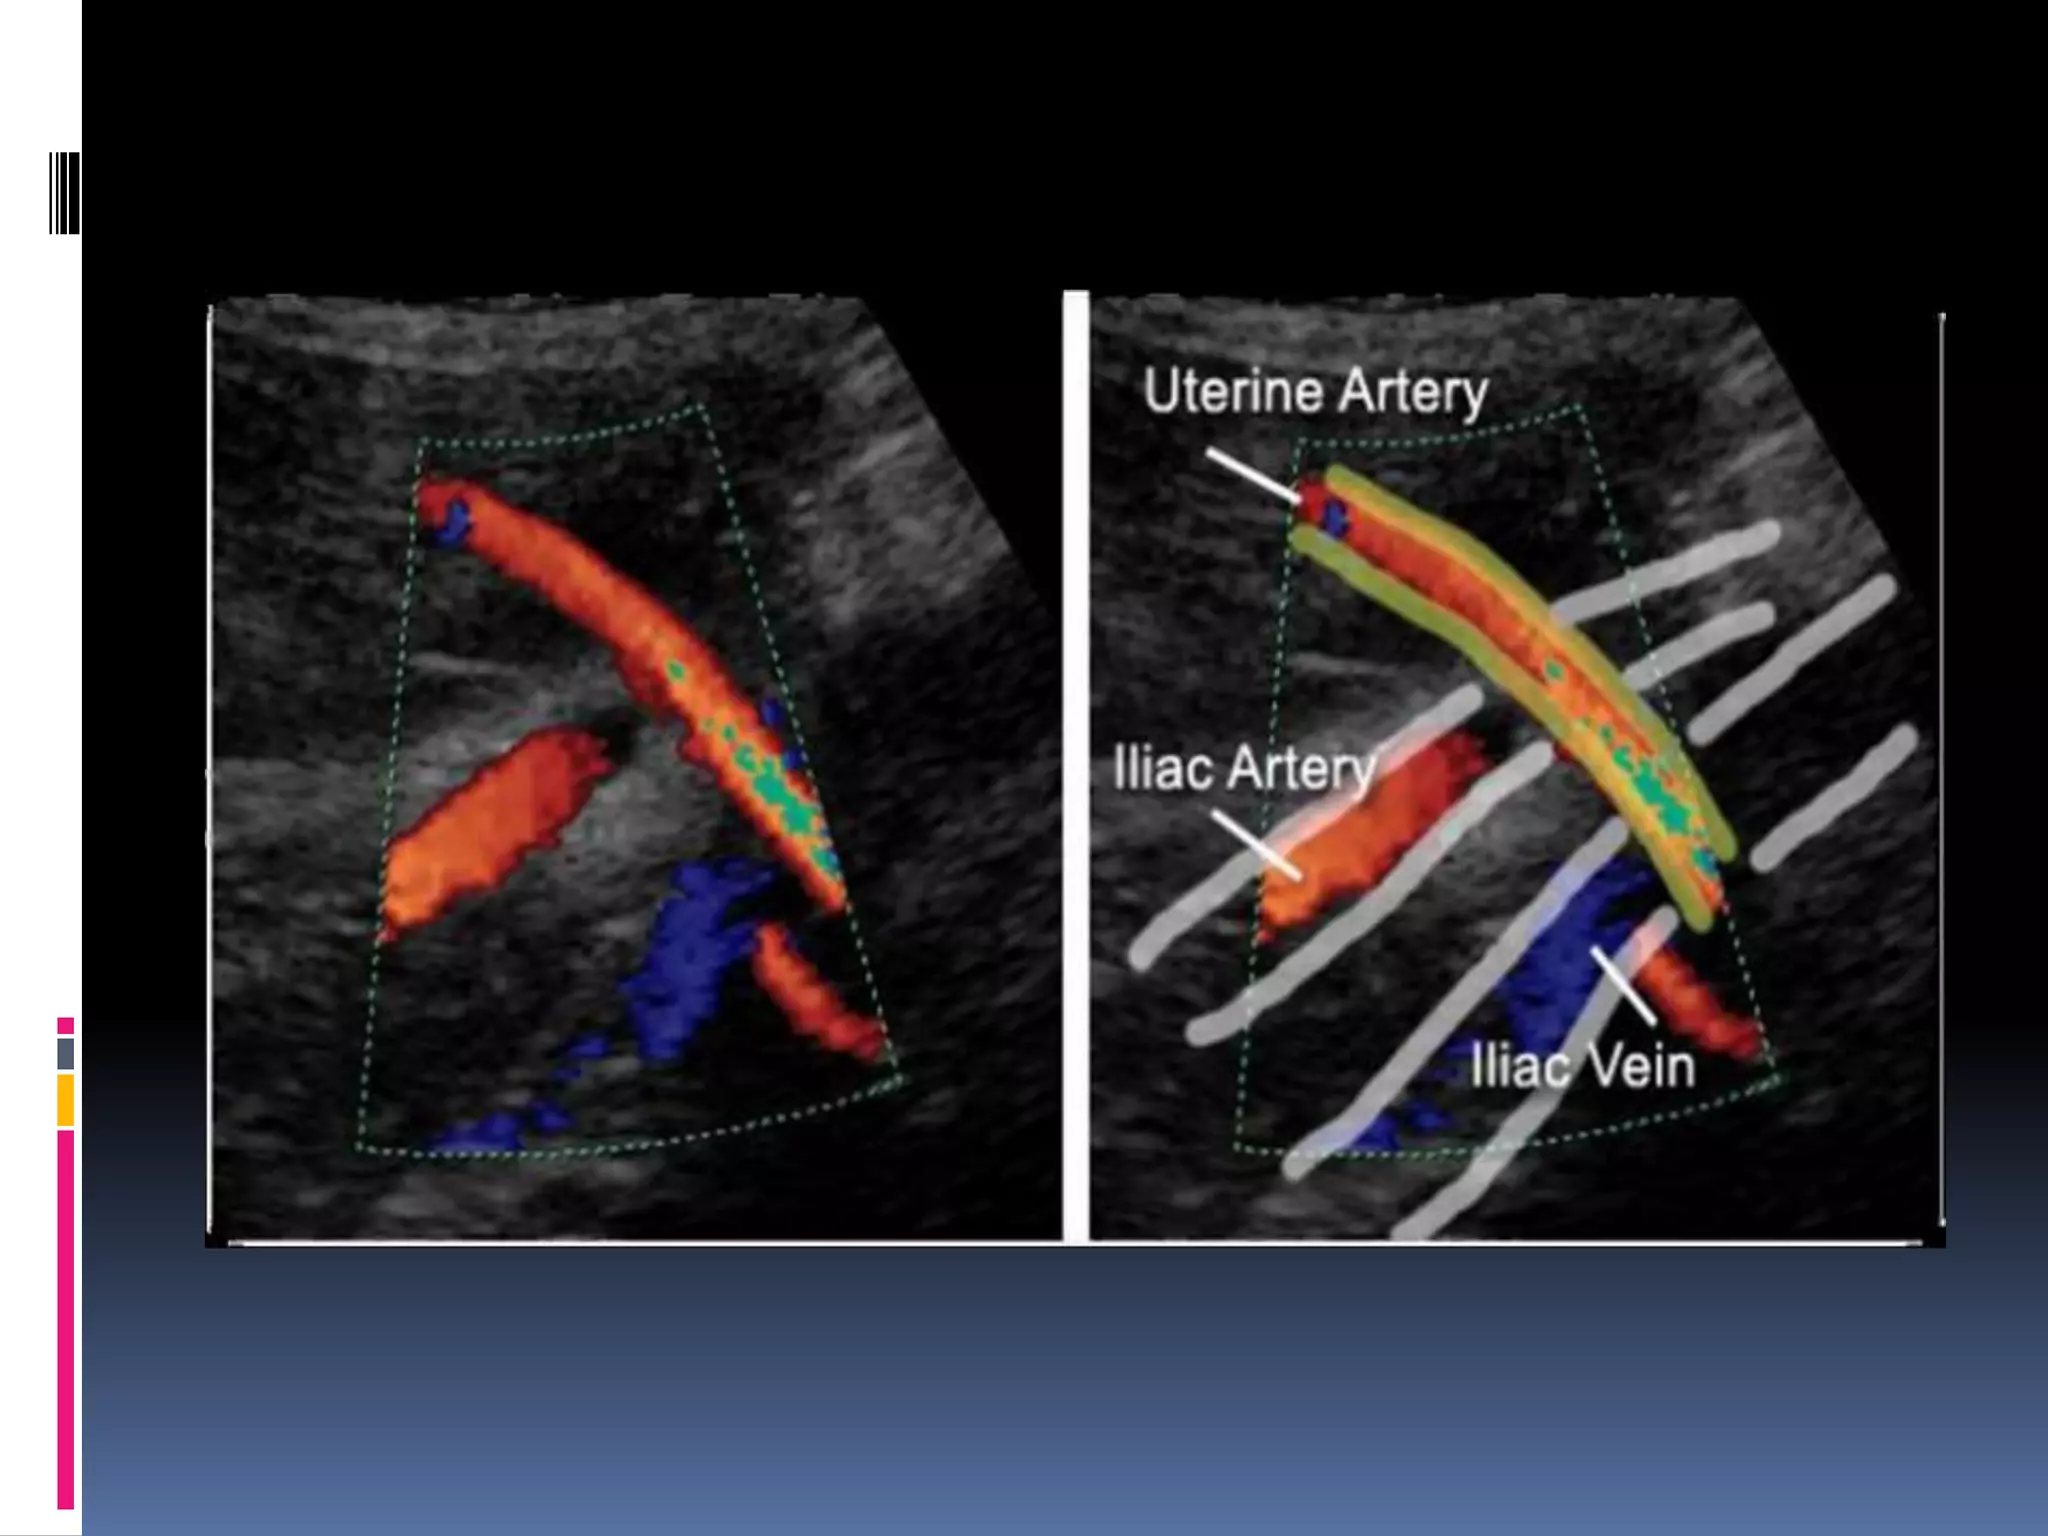

UTERINE ARTERY

 The uterine arteries branch into arcuate which lead

to spiral arteries within the myometrium.

 With advancing gestation due to trophoblastic

invasion of uterine spiral arteries , it dilates and

result in fall in the resistance to blood flow.

 Uterine artery flow in non pregnant women is 50

ml/min, and increase to 700 ml/min in 3rd trimester.

 Hence , in normal pregnancy diastolic component is

transformed from one of low peak flow and diastolic

notch to one of high flow and no diastolic notch by

18-22 weeks, PI < 1.2 is normal.

 PI> 1.45 with bilateral notches , sign of clinically

significant uteroplacental vascular ischemia.

Uterine artery score

Abnormal uterine artery flow

Increase resistance , high RI and PI

Persistent of early diastolic notch.

Score ¼-4/4